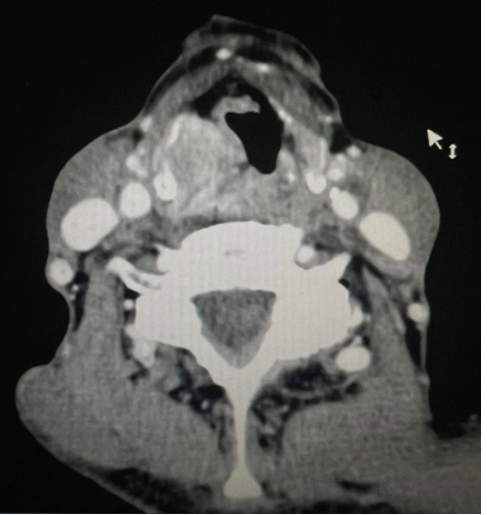

纤维喉镜、增强CT检查,明显可见患者下咽部肿瘤已经侵犯到咽侧壁及喉体区域

接诊时,经纤维喉镜、增强CT检查,发现覃爷爷的下咽部肿瘤已经侵犯到了咽侧壁及喉体区域,如果进行常规手术切除肿瘤,可能导致他今后下咽缺损后不能正常进食,若要保留下咽进食功能,肿瘤则无法切除干净。面对如此复杂的病情,李健组织了全科会诊,经过对病情严密评估和充分讨论后,决定一期切除肿瘤后使用临近颏下带蒂皮瓣修复下咽缺损。这是医院首例采用颏下皮瓣治疗下咽癌切除、全喉切除术后的下咽缺损进行治疗,填补了医院在该领域的技术空白。